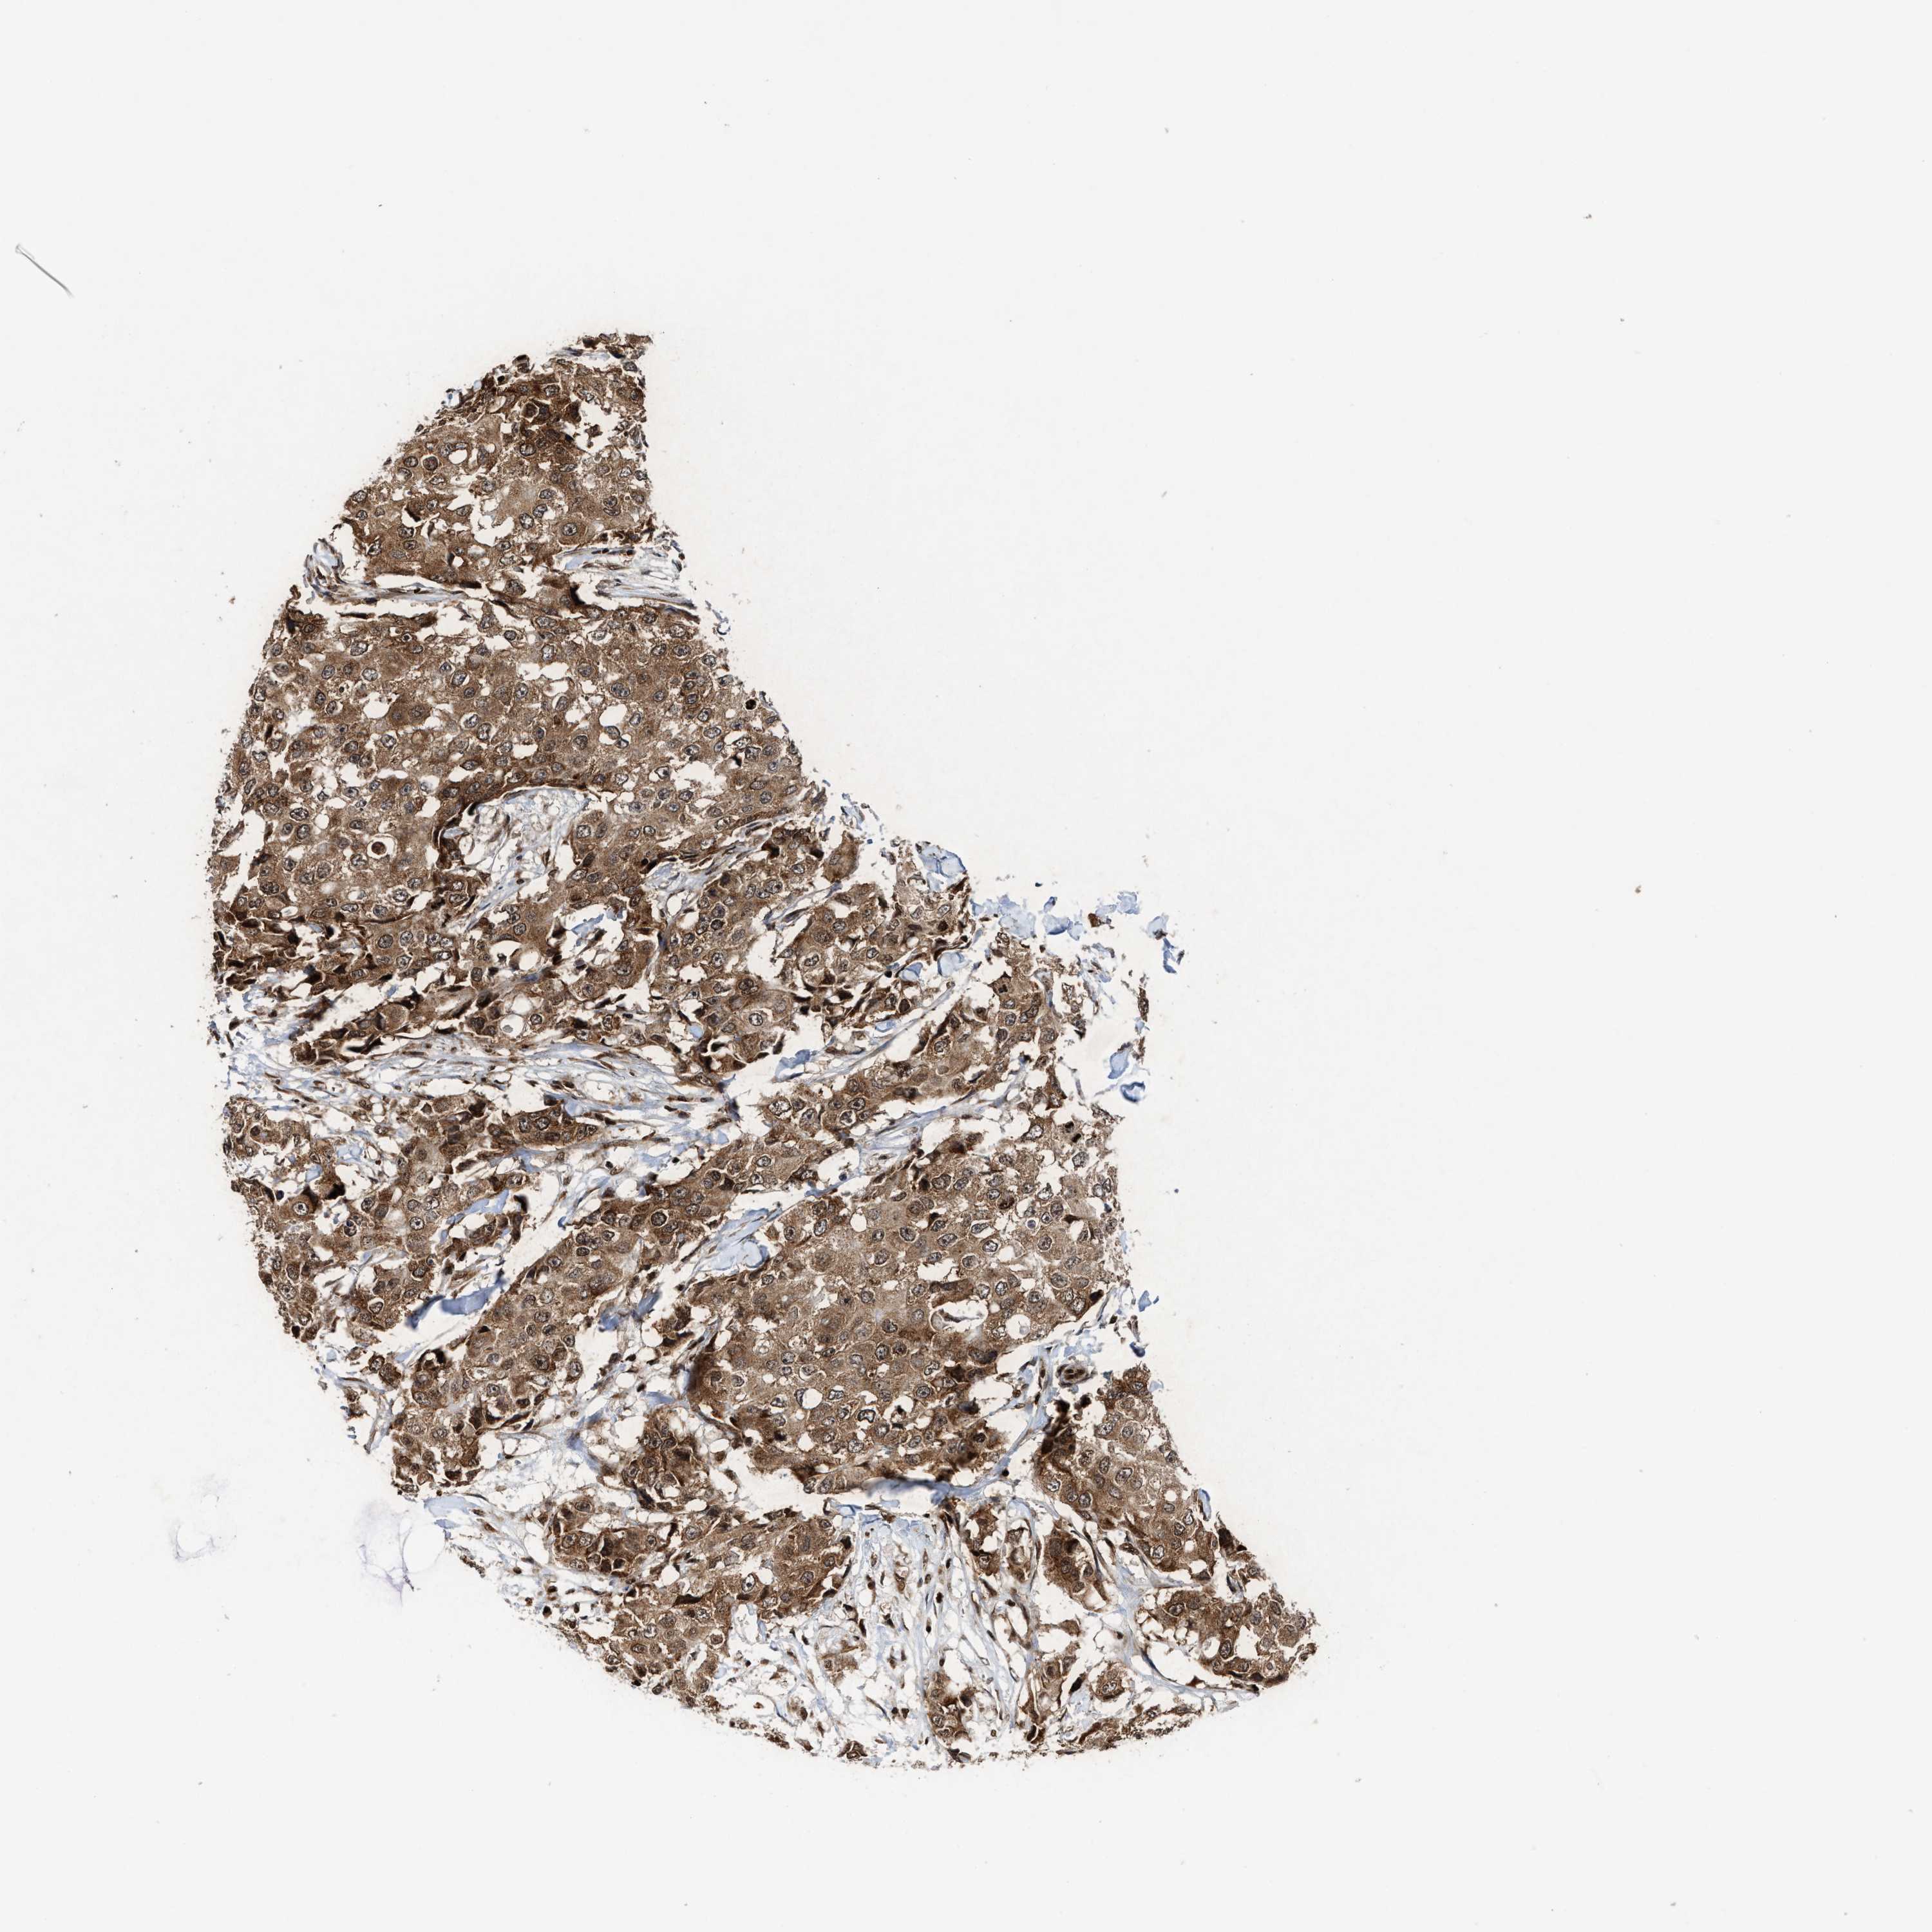

CANCER BREAST CANCER Show tissue menu

BRCA TCGA BRCA VALIDATION PROTEIN EXPRESSION